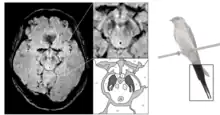

Le diagnostic de maladie de Parkinson est habituellement clinique. En théorie, la certitude du diagnostic n'est obtenue que par l'étude histologique du cerveau mais les critères diagnostiques actuellement définis permettent de faire le diagnostic sans trop de difficultés. Le scanner cérébral par tomodensitométrie des personnes atteintes de la maladie de Parkinson est habituellement normal[121]. L'imagerie par résonance magnétique sensible au fer (IRM T2*) peut être utilisée dans un cadre diagnostique. En effet, le fer peut être témoin de la mort cellulaire et le signal T2* diminue en présence de fer tandis que son inverse (R2*) augmente[122]. Dans la maladie de Parkinson, il existe une concentration en fer trop importante par rapport à la moyenne pour le même groupe d'âge au sein de la substance noire du fait de la perte de neurones dopaminergiques[123]. De plus, l'imagerie pondérée en fonction de la susceptibilité est elle aussi un marqueur fiable de la présence de fer intracérébral en étant à la fois sensible et spécifique à la maladie[124]. L'IRM T2* et l'imagerie pondérée en fonction de la susceptibilité sont toutes deux capables d'afficher le signe d'effacement de la queue d'hirondelle (swallow tail) dans la substance noire dorsolatérale. La tomodensitométrie et l'IRM sont également utilisées, en pratique clinique, pour écarter d'autres maladies pouvant engendrer un syndrome parkinsonien telles que l'encéphalite, les AVC chroniques, les tumeurs des ganglions de la base et l'hydrocéphalie[121].

Le Dat-scan est un type de scintigraphie cérébrale qui consiste à tracer les transporteurs de la dopamine de manière à pouvoir observer son parcours dans le cerveau. En effet, la tomographie par émission de positons (TEP) permet d'afficher l'activité métabolique des transporteurs dopaminergiques dans les ganglions de la base. Or, dans la maladie de Parkinson, on sait qu'il existe une mort pré-synaptique et les transporteurs de la dopamine disparaissent donc, le DaTSCAN est donc indiqué pour détecter la perte fonctionnelle des neurones dopaminergiques. Cette scintigraphie cérébrale (DaTSCAN) permettrait de montrer l'atteinte du striatum[125]. Un DaTSCAN est considéré comme normal si l'on peut observer une activité dopaminergique symétrique au sein des deux putamens des striatums, mais en cas d'asymétrie l'hypofixation dopaminergique est susceptible de dénoter une maladie de Parkinson. Le DaTSCAN corrèle bien avec le diagnostic clinique de la maladie de Parkinson[126]. De plus, une activité liée à la dopamine dans les ganglions de la base peut permettre d'exclure le syndrome parkinsonien iatrogène[121]. Une des premières indications du DaTSCAN fût de permettre la différenciation entre les tremblements essentiels des tremblements non essentiels (« parkinsoniens »)[127] et il dispose également également d'une AMM pour faire la distinction entre une démence due à la maladie d'Alzheimer ou une due à la démence à corps de Lewy. Toutefois, il faut noter que le DaTSCAN est incapble de différencier une démence associée à la maladie de Parkinson et une démence à corps de Lewy.

L'IRM de diffusion peut permettre de différencier la maladie de Parkinson des syndromes parkinsoniens atypiques ainsi que de différencier entre les sous-types moteurs de la maladie de Parkinson[128], mais sa valeur diagnostique reste sujette à débat[121].